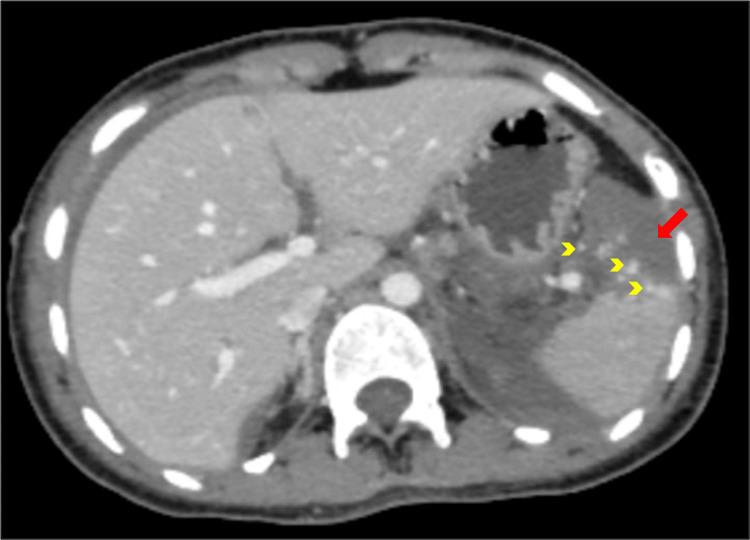

Celiac axis stenosis (CAS) is one of the most prevalent splanchnic arterial pathologies. It seldom results in clinically severe ischemic bowel disease because of the rich collateral circulation from the superior mesenteric artery. Knowledge about the collaterals in celiac artery stenosis guides various interventional procedures. Here, we describe a case of a 19-year-old female with American Association for the Surgery of Trauma (AAST) grade IV splenic injury found to have CAS. Distal splenic artery embolisation was performed via the collateral pathway through the pancreaticoduodenal arcade.

腹腔干狭窄(CAS)是最常见的内脏动脉病变之一。由于肠系膜上动脉丰富的侧支循环,它很少导致临床上严重的缺血性肠病。了解腹腔干狭窄中的侧支循环有助于指导各种介入手术。在此,我们描述了一例19岁女性,其因美国创伤外科协会(AAST)IV级脾损伤而被发现患有CAS。通过胰十二指肠动脉弓的侧支途径进行了脾动脉远端栓塞。